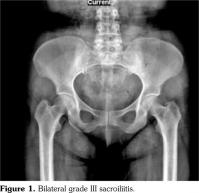

A 43-year-old female patient applied to our clinic with complaints of low back pain, morning stiffness and swelling in ankles. The patient had been followed-up in a university hospital with the diagnoses of FMF and SpA for eight years. She was on treatment of sulfasalazine 2 g/day, colchicine 4x0.5 g and acemetacin 120 mg/day. Patient’s rheumatologic questioning revealed oral aphthae, inflammatory low back pain, morning stiffness, episodic arthritis in lower extremities, febrile attacks, genital ulcerations healing with scarring, and erythema nodosum. When her anamnesis was deepened, her abdominal attacks accompanied by fever were discovered. She stated that her complaints and frequency of attacks had diminished after colchicine treatment. Therefore, she was diagnosed as FMF according to Tel- Hashomer diagnostic criteria for FMF.(5) Patient’s systemic physical examination was normal. In locomotor examination, sacroiliac compression tests were bilaterally positive. Modified Schober was 6.5 cm, hand finger-floor distance was 5 cm, occiput to wall distance was 7 cm, tragus to wall distance was 19 cm, and chest expansion was 5 cm. Also, her ankles were bilaterally warm, swollen and tender with normal range of motion. She had enthesitis in her right Achilles tendon and fifth lumbar spinous process. In her family history, her daughter also had FMF. Her laboratory analysis results were as follows; erythrocyte sedimentation rate: 23 mm/h, C-reactive protein: 1 mg/dL, hemoglobin: 9.2, human leukocyte antigen (HLA)-B27: negative, HLA-B51: positive. Pelvis graphy showed bilateral grade III sacroiliitis (Figure 1). The pathergy test was negative. Her coronary computed tomography angiography and ECHO results, which were performed due to her dyspnea, were normal. Her endoscopic gastrointestinal system evaluation revealed erosion in fundus, cardia and duodenum. The patient fulfilled the Assessment in Spondyloarthritis International Society classification criteria with definite radiographic sacroiliitis according to modified New York criteria and inflammatory low back pain, enthesitis, arthritis in lower extremities, and good response to nonsteroidal anti-inflammatory drugs. The patient was also diagnosed with BD on having oral aphthae, genital ulcerations and erythema nodosum according to criteria of international study group for BD.(6)